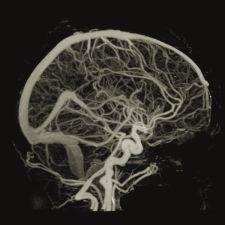

Toshiba will introduce its advanced software package, Sure Subtraction, for its Aquilion CT line, reportedly created to reduce CT examination time for patients exhibiting symptoms of neurological disorders by automating and streamlining bone subtraction.

The application is exclusive to Toshiba and is an option for its 8-, 16-, 32- and 64-slice CT systems. Given the software’s ability to detect and successfully subtract bone from images, the system offers multiple clinical applications, including cerebral aneurysms, ICA, basilar artery, cases with stenosis or occlusion, calcification, hypervascular tumors and scanning from neck to head.